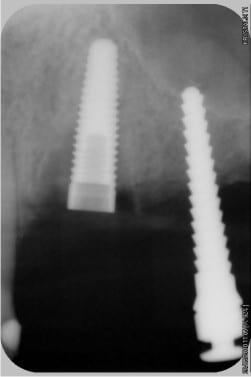

La pano, excusez, j'ai perdu l'habitude d'eugénol...

04/06/2010 à 20h48

NB: les implants distaux gauches vont être retirés, il étaient déjà là avant que je n'intervienne.